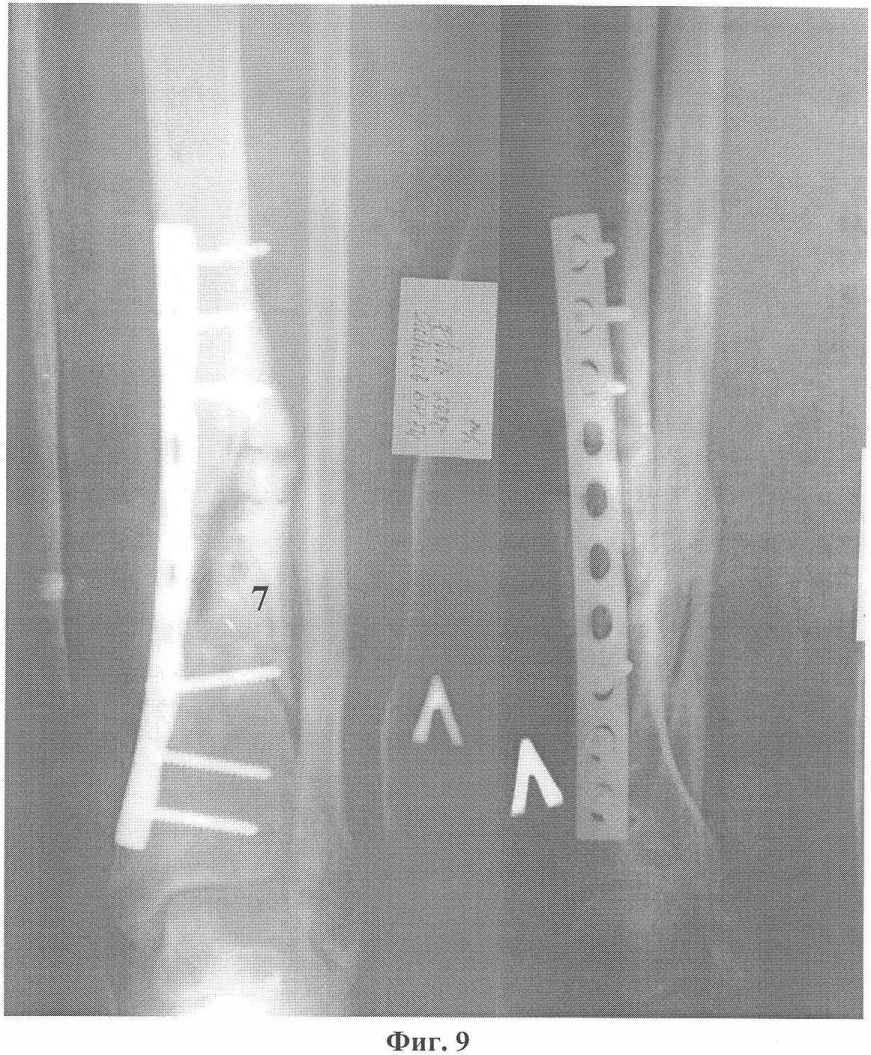

Фиг.12. Восстановление непрерывности большеберцовой кости через 3 месяца после операции.

Больной Н., 55 лет, 23 июня 2005 года в результате бытовой травмы получил закрытый оскольчатый перелом обеих костей левой голени. Доставлен в городскую клиническую больницу г.Москвы, где был произведен остеосинтез большеберцовой кости левой голени пластиной АО с ограниченным контактом. Послеоперационный период протекал без осложнений. Проведено восстановительное лечение, включающее ходьбу с костылями с дозированной, постепенно увеличивающейся нагрузкой на оперированную конечность. Через 3 месяца после операции начал ходить с палочкой с полной нагрузкой на левую стопу. Однако при ходьбе отмечал умеренные боли в области перелома. Динамический рентгеноконтроль демонстрировал замедленную консолидацию перелома большеберцовой кости на фоне сросшегося перелома малоберцовой кости. В мае 2006 года боли в голени при ходьбе усилились. При контрольной рентгенографии обнаружен ложный сустав большеберцовой кости с переломом накостной металлоконструкции и миграцией винтов (фиг.8). 6 июня 2006 года под общим обезболиванием сломанная пластина была удалена с выполнением операции на ложном суставе по разработанному способу (фиг.9). После снятия швов и ликвидации отека произведена иммобилизация конечности укороченной циркулярной повязкой Scotchcast (до коленного сустава), и больной приступил к нагрузке в дозированном режиме. К концу 3-го месяца ходьба с полной нагрузкой без дополнительной опоры (фиг.10) в иммобилизирующей повязке (фиг.11), болей в голени нет, повязка снята, рентгенологически определяется сращение перелома большеберцовой кости (фиг.12). После проведения 2-х недельного реабилитационного курса функция конечности восстановлена в полном объеме (фиг.13, 14).